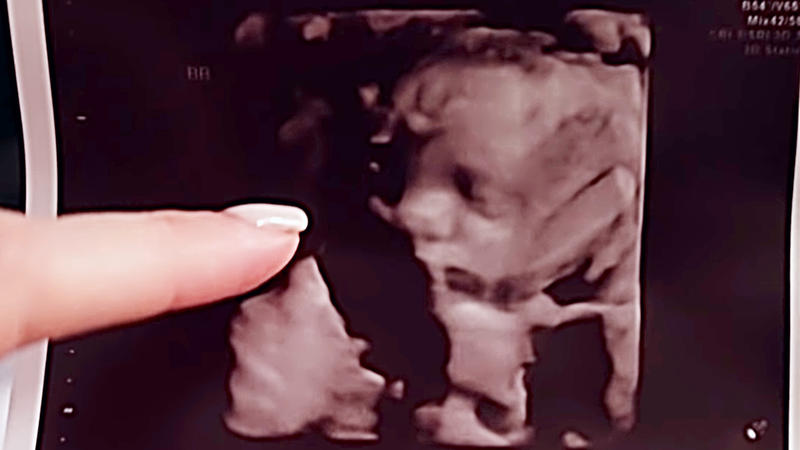

Well, this meant that she saw success in carrying the three babies without any severe complications. Each and every person in the couple’s lives were happy to see and hear that the babies were fine until then and that everything went as planned. But, there was one last push she needed to make so that her delivery would go smoothly!